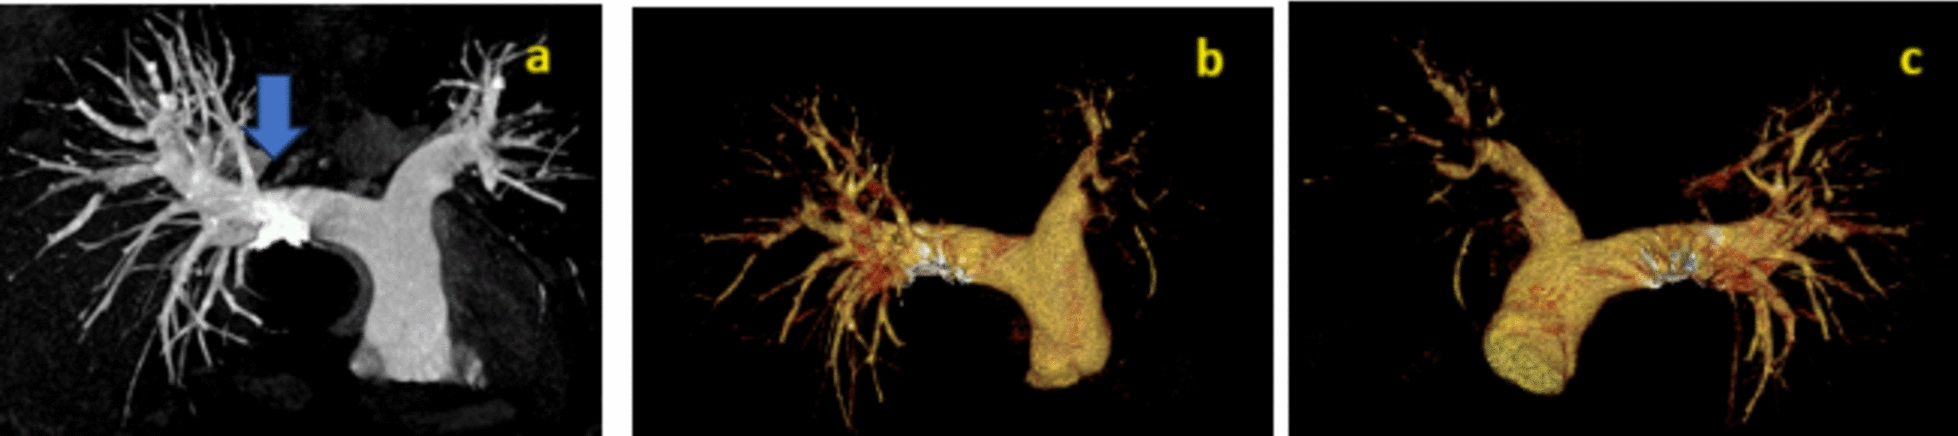

Case presentation: A 45-year-old Indian male presented with multiple episodes of fever with chills, palpitations, dyspnea, right upper abdominal pain, bilateral lower limb edema, and petechia for 20 days. On examination, tachycardia, tender hepatomegaly, and reduced air entry in the right lower lobe of the lung were observed. Ultrasound revealed an abscess in the left lobe of the liver about 150 cc in volume, abutting the inferior vena cava with rupture into it. Contrast-enhanced computed tomography imaging showed 5.7 × 6.2 × 5.4 cm segment IV A liver abscess with capsule breach into the intrahepatic vena cava and thrombus extending up to the right atrium was observed. Computed tomography-pulmonary angiography revealed a right atrium thrombus with bilateral pulmonary artery thrombus and parenchymal infarcts. Raised D-dimer, protein C and S deficiency was observed. The patient was managed by needle aspiration of abscess, anticoagulation, and antibiotics.